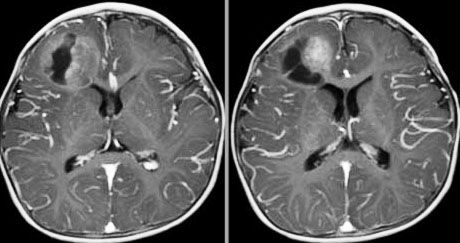

AT/RTのMRI画像

AT/RTのMRI像はさまざまです。乳幼児のgrade IVの悪性腫瘍ですから,増大速度が極めて速く,巨大で,腫瘍周辺脳浮腫が強く,ガドリニウムで強く増強されるというのが一般的です。硬膜を侵し頭蓋骨破壊を伴って頭蓋から外に膨隆してくるのもあります。多くは腫瘍内部に壊死が見られ壊死性のう胞が形成されます。CT/MRIで、腫瘍血流が豊富で細胞密度が高いという所見は重要な点です。

でもこの例(上の画像)の様に,mass effectも軽度で腫瘍周辺浮腫も目立たないものも珍しくはありませんし,他の胎児性脳腫瘍とは画像診断で鑑別することはできません。